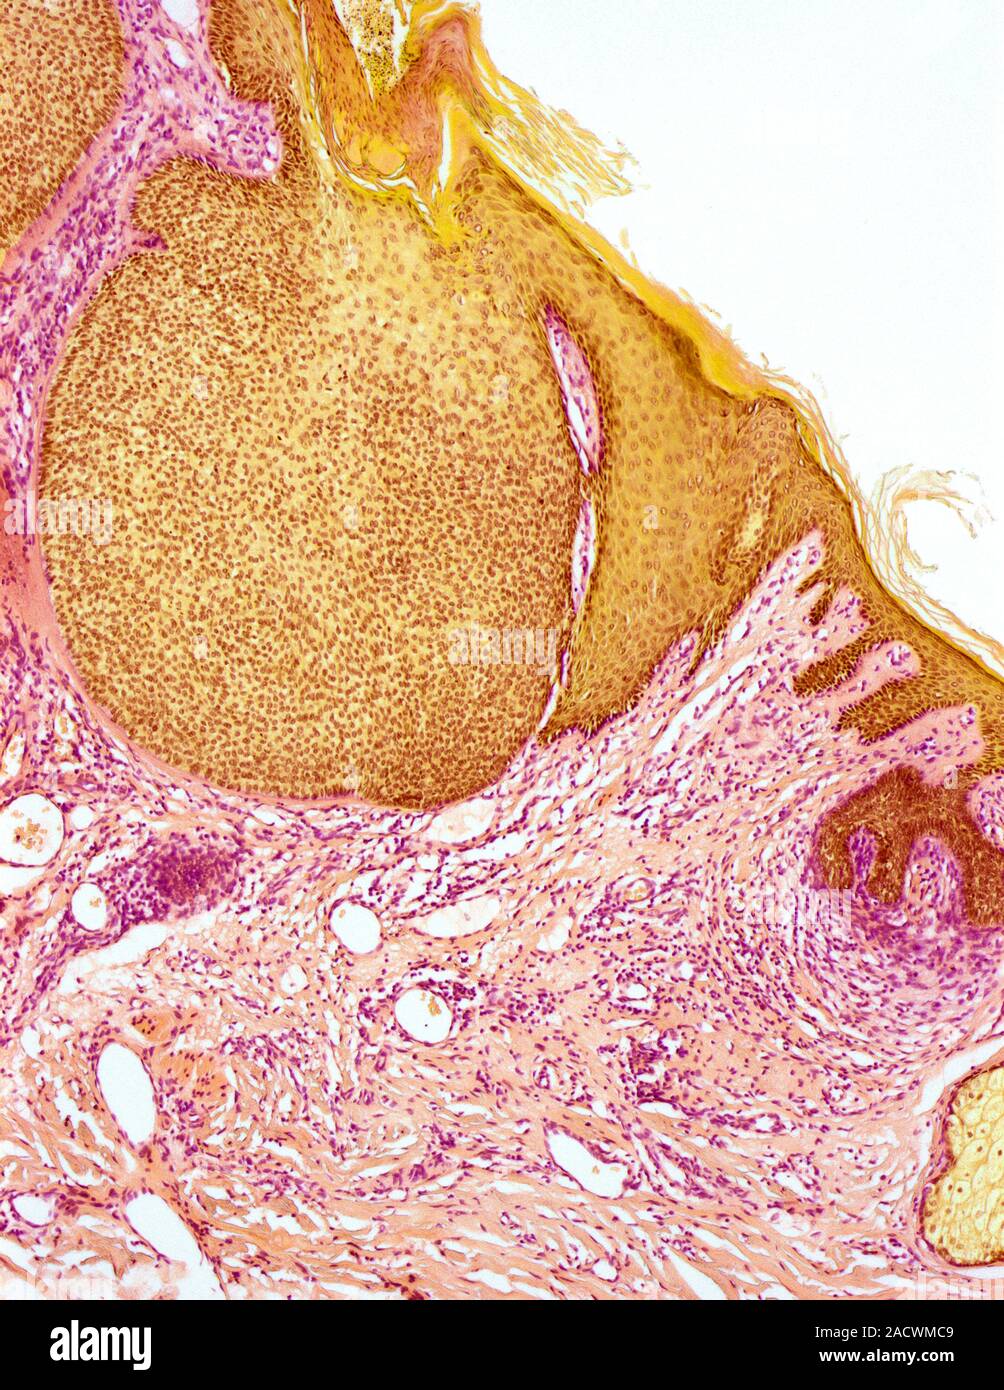

Skin cancer. Light micrograph of a section through a basal cell Basal Cell Carcinoma Ulcer Metastasis is rare, but local growth can be highly destructive. Most bccs are painless, although sometimes they can be itchy or. Basal cell carcinoma (bcc), previously known as basal cell epithelioma, is the most common cancer in humans. This common skin cancer has several types and causes small bumps or open sores on the. Basal cell carcinomas arise from keratinocytes. Basal Cell Carcinoma Ulcer.

Skin cancer. Light micrograph of a section through a basal cell Basal Cell Carcinoma Ulcer Hence the name “rodent ulcer”. A rodent ulcer is an uncommon and outdated name for basal cell carcinoma (bcc), a type of skin cancer. Basal cell carcinoma (bcc), previously known as basal cell epithelioma, is the most common cancer in humans. If left untreated, bccs can eventually cause an ulcer; Most bccs are painless, although sometimes they can be itchy. Basal Cell Carcinoma Ulcer.